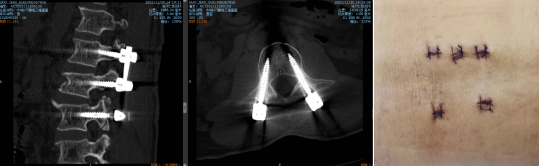

最终,孟磊副主任医师团队在天玑骨科机器人定位下,通过3D图像扫描规划手术中椎弓根螺钉的进钉点、置钉方向以及置钉深度。根据机器人系统导航,通过机械臂精准定位置钉位置,医生只在置钉部位切开约2cm切口,不损伤其它椎关节,保障神经安全和手术的有效性。

术后,大叔的腰也不疼了,背也挺直了,恢复两天,就下地锻炼行走了。

孟磊副主任医师介绍,“机器人强大的光学追踪系统可以进行三维透视扫描,能看到人眼看不到的地方,还可以实时监控手术每一个环节;大大减少人手置钉产生的误差,通过精确的定位系统将螺钉精准地置入到最理想的位置,一步到位。尤其对微创术式、高风险区域具有明显优势。”